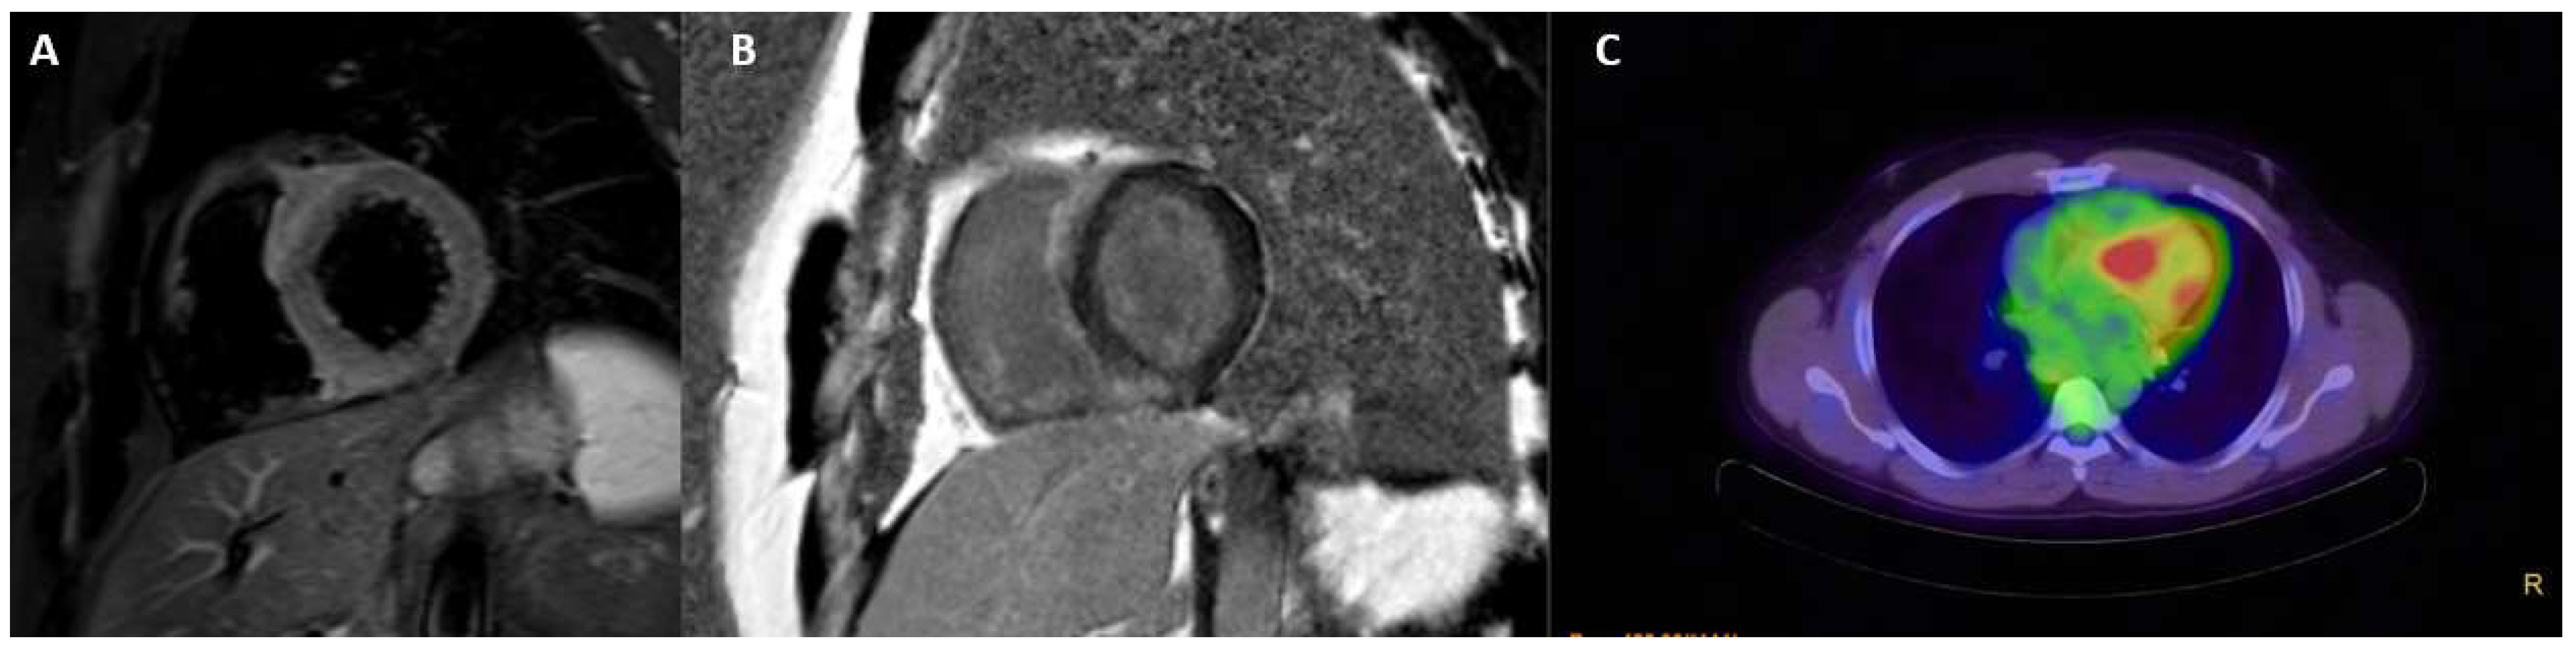

3.7. Cardiac Sarcoidosis